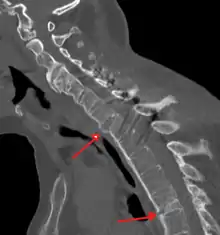

X-rays

The earliest changes demonstrable by plain x–ray shows erosions and sclerosis in sacroiliac joints. Progression of the erosions leads to widening of the joint space and bony sclerosis. X-ray spine can reveal squaring of vertebrae with bony spur formation called syndesmophyte. This causes the bamboo spine appearance. A drawback of X-ray diagnosis is the signs and symptoms of AS have usually been established as long as 7–10 years prior to X-ray-evident changes occurring on a plain film X-ray, which means a delay of as long as 10 years before adequate therapies can be introduced.[25]

Options for earlier diagnosis are tomography and MRI of the sacroiliac joints, but the reliability of these tests is still unclear.

CT scan showing bamboo spine in ankylosing spondylitis